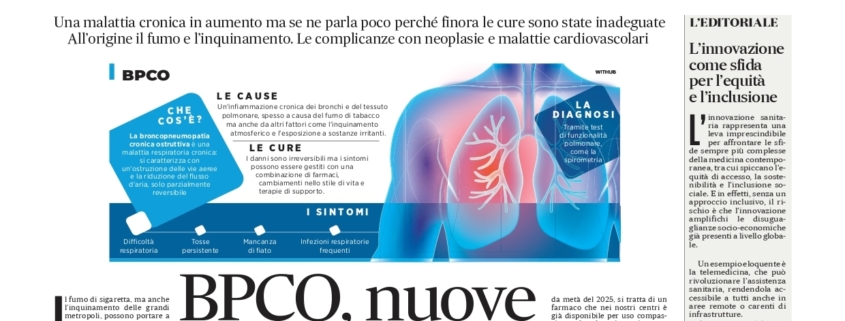

Oggi on line un nuovo capitolo del viaggio che il Network editoriale PreSa ha intrapreso ormai da anni nel mondo della Prevenzione e della Salute. Sulle pagine de “Il Mattino”, in questo nuovo numero dello speciale si parla di una malattia poco conosciuta e spesso sottovalutata: la Bronco-Pneumopatia Cronica Ostruttiva (BPCO). Come riconoscerla, quali sono i sintomi e i fattori di rischio, come affrontarla grazie a terapie innovative. Tanto spazio, poi, alla medicina del futuro e alle strategie migliori per affrontare i grandi temi di politica sanitaria posti dalla modernità. Marco Trabucco Aurilio (presidente della Fondazione MESIT), propone una riflessione sul fatto che l’innovazione è la sfida da vincere per favorire equità e inclusione e, poi, tanto spazio all’Health Innovation Show – l’evento che la Fondazione MESIT ha promosso e che si pone come uno spaccato unico dei nuovi scenari, con sistemi informatici intelligenti che accelerano le diagnosi migliorando qualità ed effetti delle terapie. Insomma, uno speciale da leggere tutto d’un fiato.